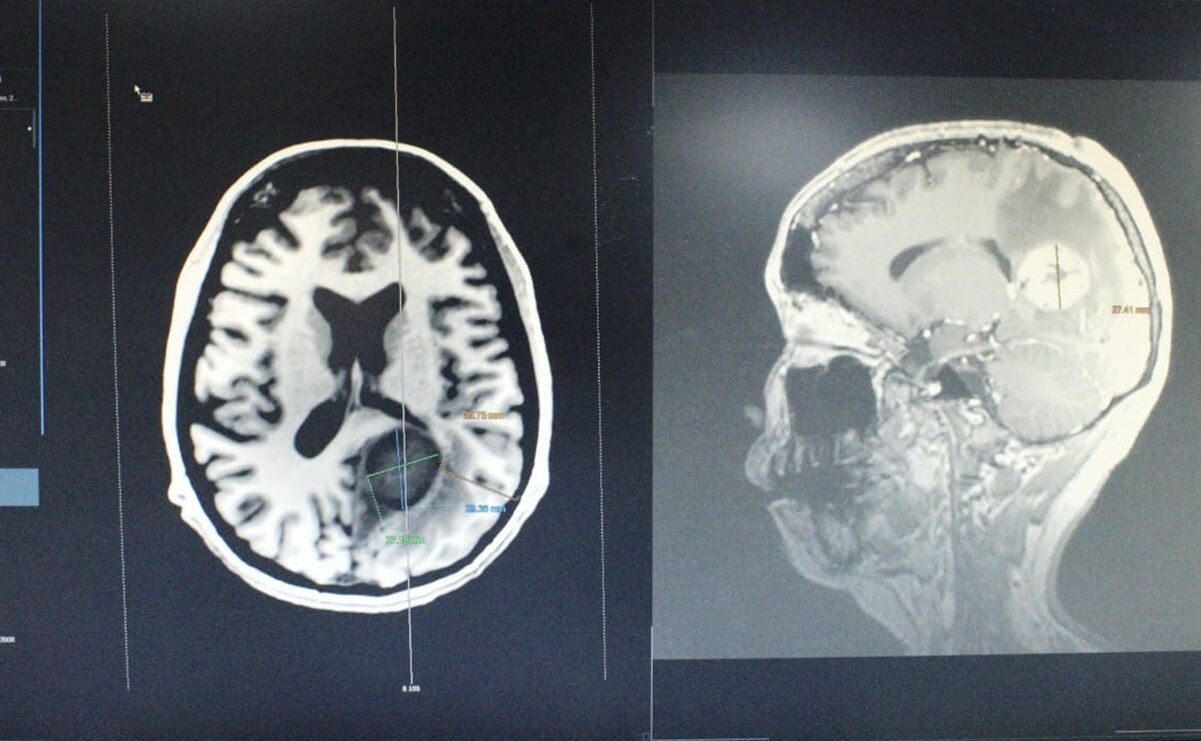

Primero la operaron de la vesícula, después del corazón y finalmente especialistas del ISSSTE le detectaron el tumor en el cerebro